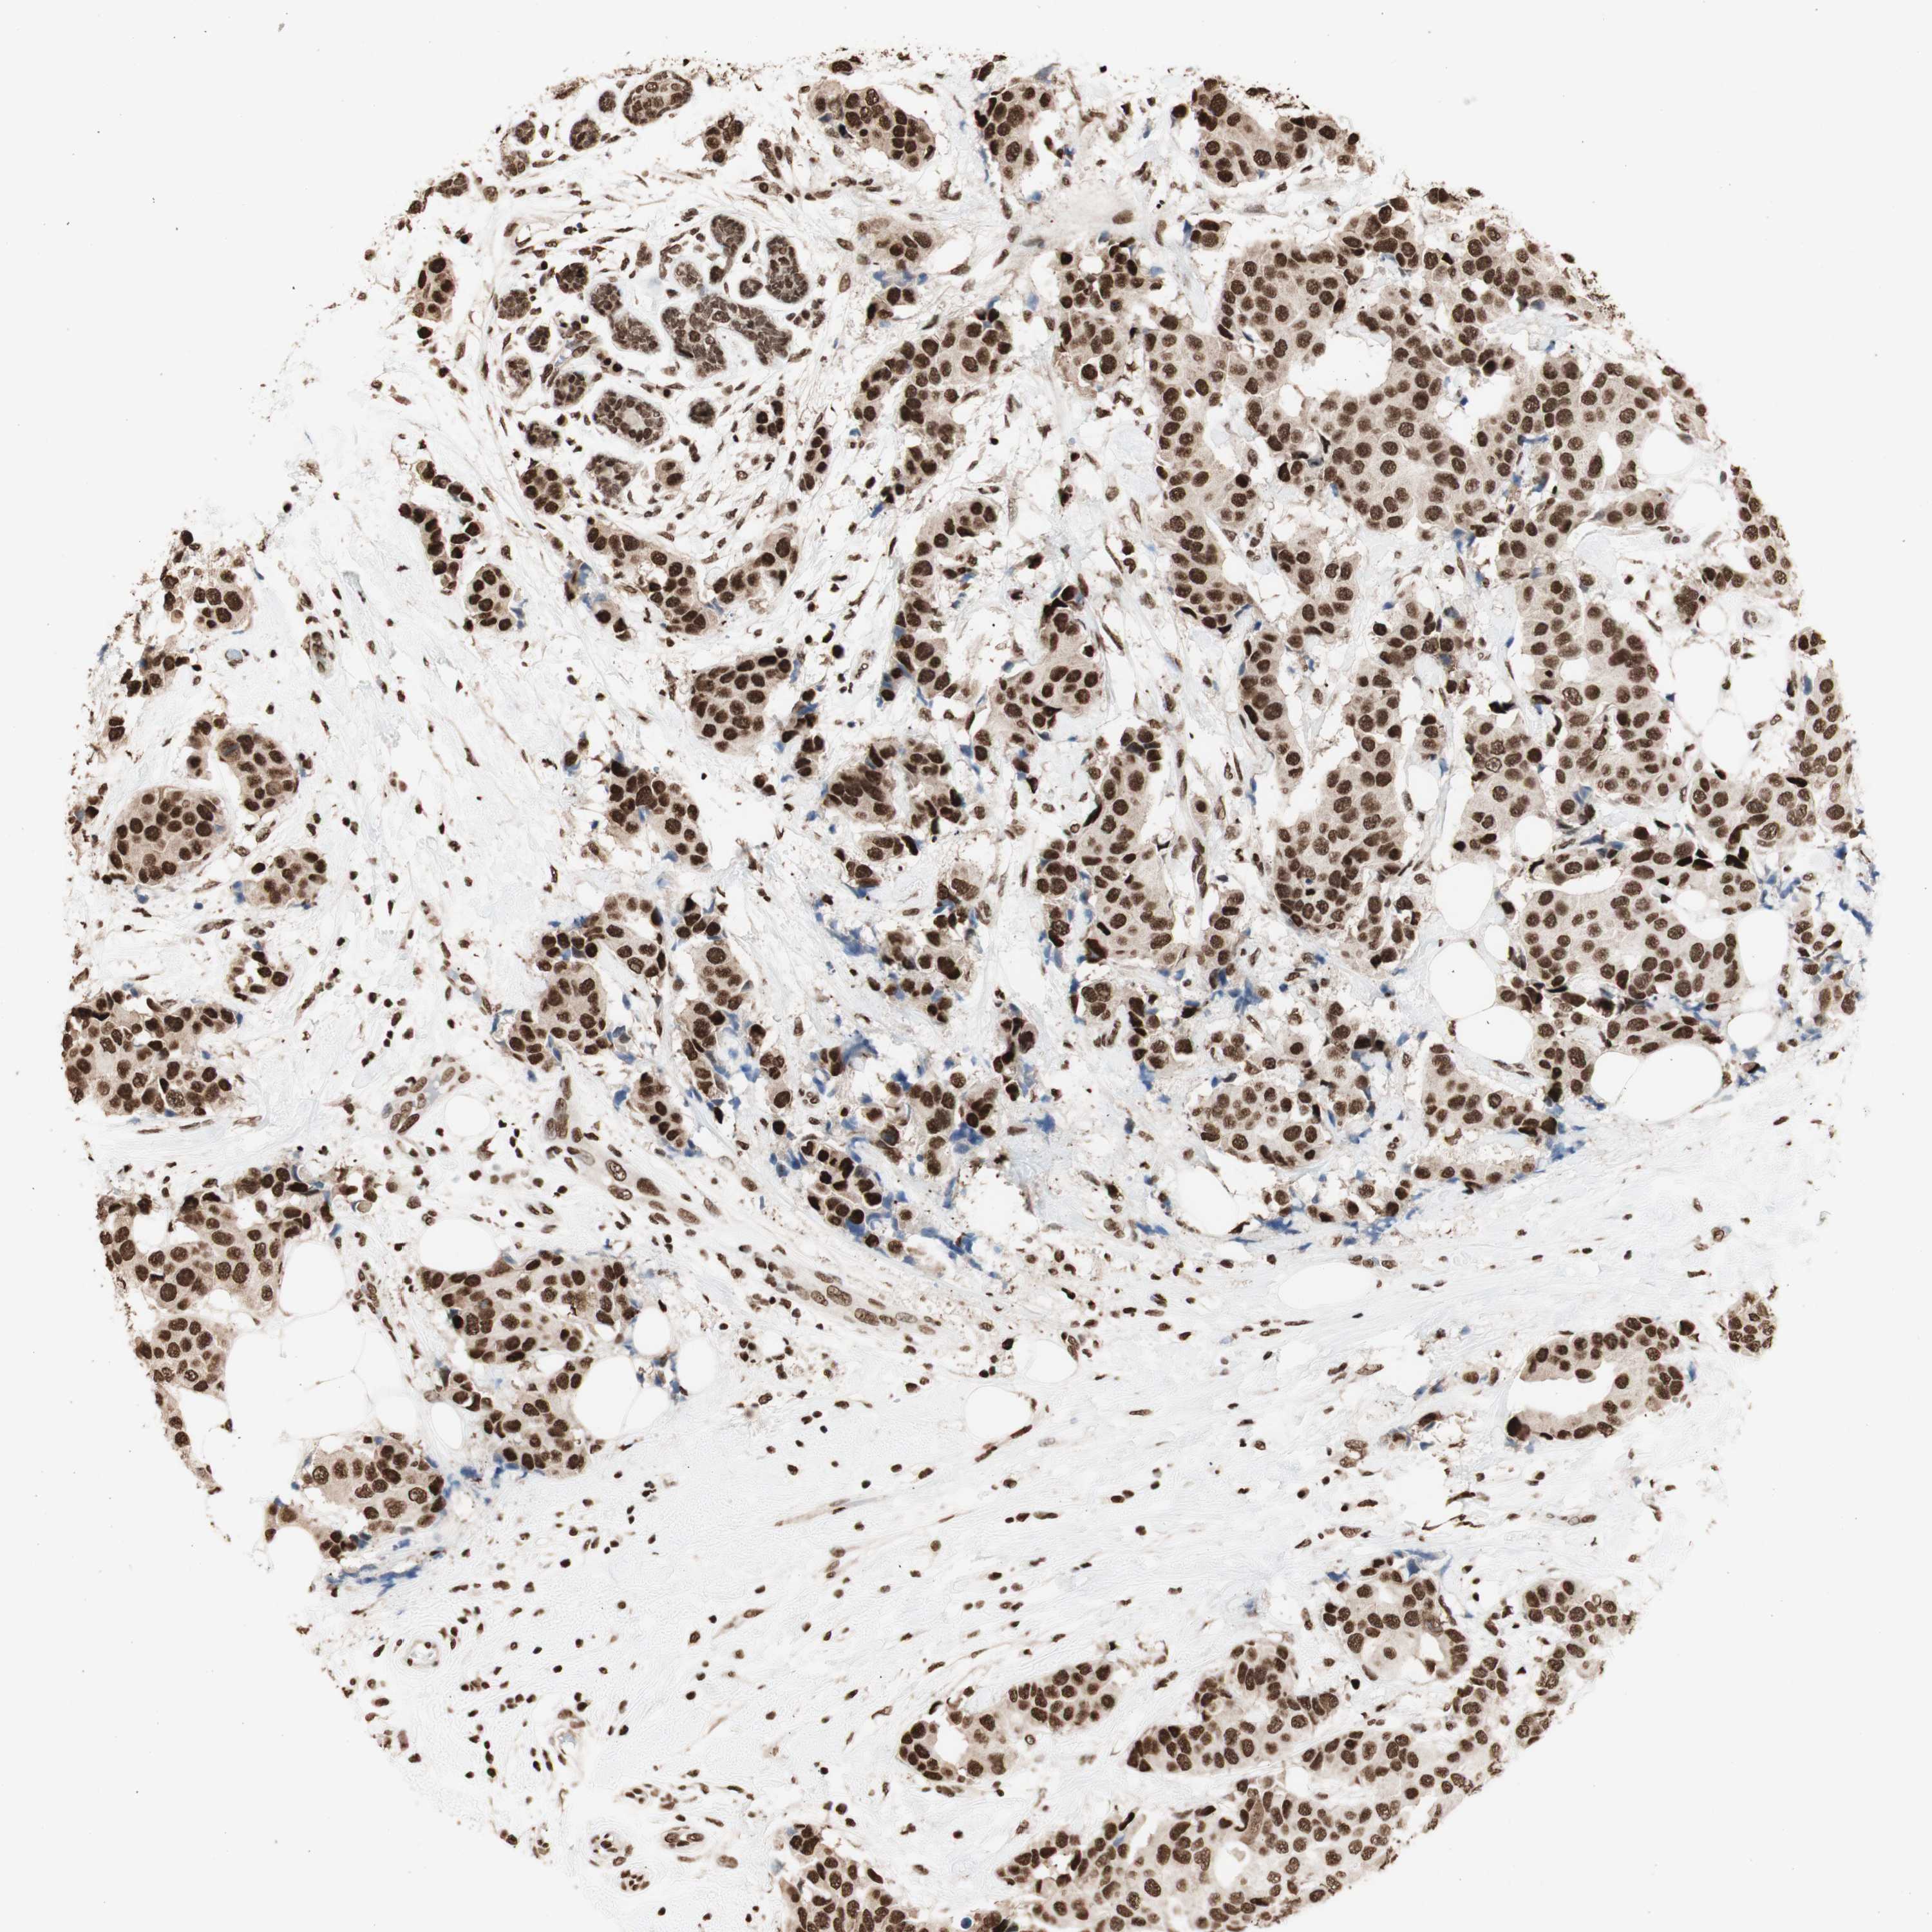

CANCER BREAST CANCER Show tissue menu

BRCA TCGA BRCA VALIDATION PROTEIN EXPRESSION